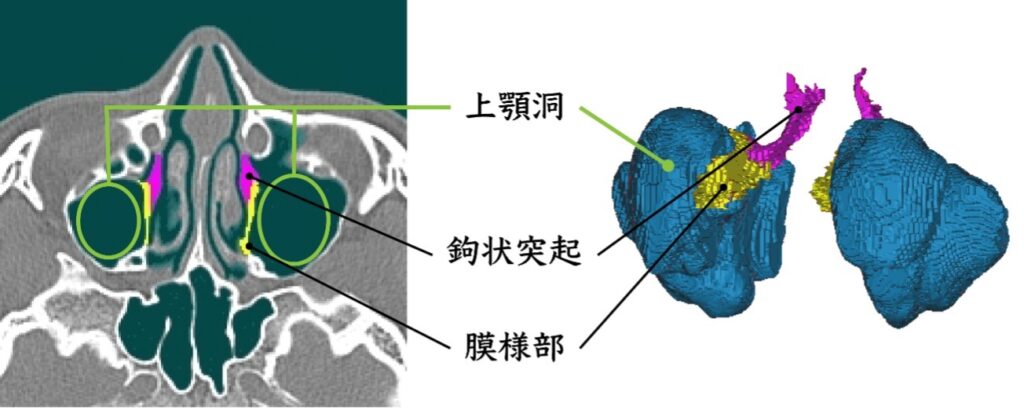

模擬手術と音響シミュレーションによる鼻副鼻腔の音響特性の解明について、現在は副鼻腔の部位の1つである上顎洞の開放範囲(切除規模)の違いによる音声変化への影響の検討に取り組んでいます。本研究室では患者のCT(Computed Tomography)データから鼻副鼻腔を含めた声道形状を抽出し、抽出したデータを用いて手術(模擬手術)を行います。そのデータに対して音響シミュレーションを用いることで、手術後の音声変化を予測する手法を確立しました。この手法の確立によって実際に実験を行うことが難しい、開放範囲の違いによる音声変化の違いを検討することが可能となりました。

(緑:模擬手術による切除範囲)

そこで現在は、2024年度の研究にて副鼻腔のうち特に音声変化への影響が大きいことが示された上顎洞の開放範囲による音声変化について検討をしました。上顎洞の開放範囲は鉤状突起と膜様部の切除規模によって決まります。鉤状突起とは骨の突出部のことであり、膜様部は鉤状突起と接続している薄い粘膜のことです。これらの部位の切除によって副鼻腔の容積が拡大します。検討の結果として、上顎洞の開放範囲が小さい程音声変化が小さく、範囲が大きい程音声変化が大きくなる可能性が示唆されました。しかし、被験者によっては開放範囲が小さいのにも関わらず音声変化が大きくなる傾向も見られました。